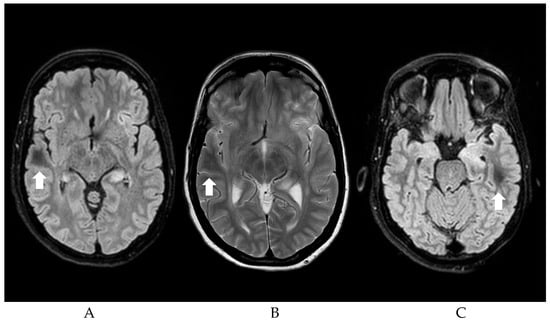

Consequently, the most commonly described etiologies of DWM and seizures will be discussed here. Regardless of etiology, the occipital lobes seem to be the most common localization of DWM in patients with seizures (32.2%), followed by parietal (27.7%), frontal (21.9%), and temporal lobe (18%). Motor symptoms are the most commonly represented clinical manifestations (64.4%), followed by visual symptoms (37.5%). Figure 1 shows an example of the DWM.

Figure 1. (A,C) FLAIR sequences showing Subcortical localization of DWM (Dark White Matter, see arrows) of a patient with NCSE; (B) T2 Sequences showing DWM.